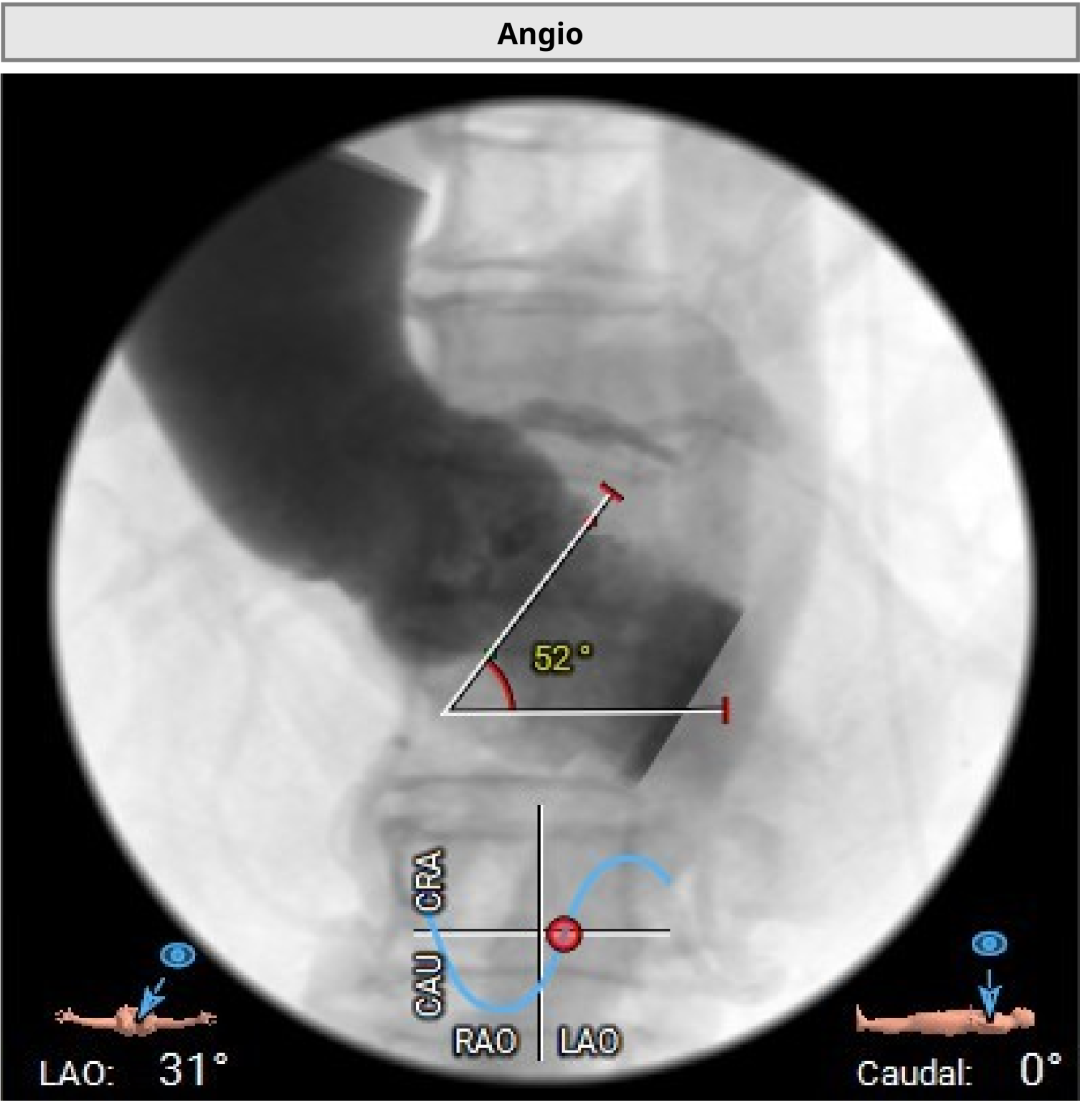

术中,因患者主动脉弓形态较复杂,器械通过一度受阻。团队根据术中情况及时调整策略,最终顺利完成过弓、跨瓣和瓣膜释放。造影及经胸超声显示,瓣膜位置理想、功能良好,左右冠脉血流通畅,未见瓣周漏及血管并发症。

▲左右重合位评估

▲左冠切线位评估